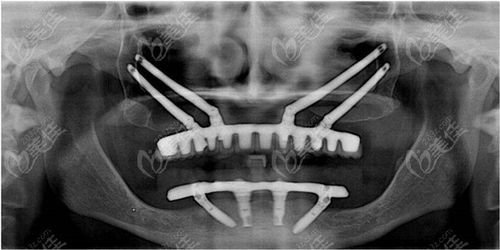

种植牙穿颧有没有后遗症?这是许多需要进行种植牙手术的人们所担心的问题。穿颧骨种植牙是一种比较复杂的手术,需要在颧骨(颧弓)骨质中进行植骨,以提供足够的支撑力。在穿颧骨种植牙的过程中,患者和医生都需要注意一些风险和注意事项。本文将从几个方面对种植牙穿颧有没有后遗症进行详细的阐述,帮助读者更好地了解穿颧骨种植牙手术。

穿颧骨种植牙虽然具有许多优点,但是也存在一定的风险。在进行穿颧骨种植牙手术前,医生需要对患者进行全面的检查,以确定患者是否适合进行此项手术。以下是穿颧骨种植牙的风险和注意事项:

1. 龈内动脉损伤:颧骨穴位与龈内动脉相邻,手术时需要特别小心,以避免对龈内动脉造成损伤。

2. 颧骨骨质过于薄弱:如果患者颧骨骨质过于薄弱,可能会出现植入体松动、移位等问题。